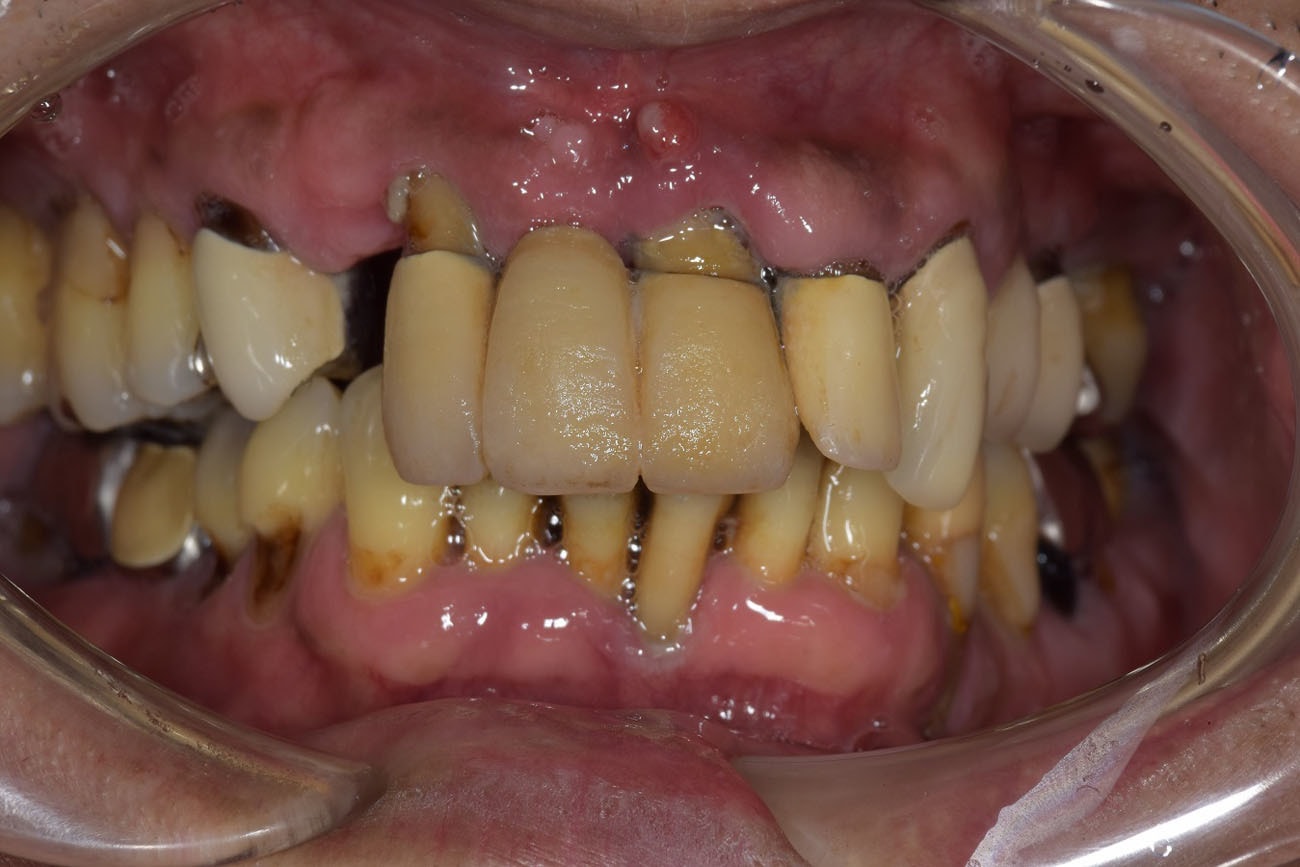

治療前

治療前は、お口の中が重度の歯周病にかかっており、歯が大きく動いていたため、ものを噛むことが出来ない状態でした。